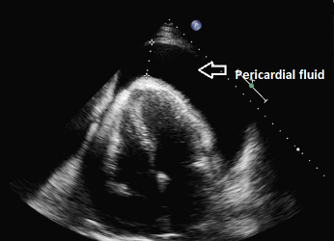

Cardiac tamponade

This complication may occur if the tip of the PICC line lies within the heart. To avoid this complication the tip of all PICC lines must be seen clearly outside of the cardiac silhouette. See advice on imaging above. Cases have been recorded where the tip appears to have migrated after the initial X-ray. To guard against this, the tip of the line should be noted on any subsequent x-ray taken for other reasons. The following symptoms and signs may alert the clinician that tamponade has occurred

Cardiac tamponade can be easily diagnosed using an ultrasound scanner as there will be a large collection of fluid around the heart. See appendix for the procedure for aspiration of a cardiac tamponade.

![]() |

Cardiac tamponade is a rare complication of PICC line use in neonatal units. It is a medical emergency, with associated morbidity and mortality. Literature suggests an incidence of 0.76% to 3% in infants with PICC lines. Retrospective data from the UK estimate an incidence of 0.2%, with a mortality of 0.7 per 1000 neonates. Initial resuscitation should be methodical and follow recognised life support guidelines. Siting catheter tips outwith the cardiac border does not completely abolish the risk of pericardial effusion, or cardiac tamponade.12

Pericardiocentesis should only be performed by skilled operators, under ultrasound guidance, unless a delay in treatment would be life threatening. If it is not possible to await ultrasound-guided drainage, emergency pericardiocentesis should be attempted by the most experienced neonatal practitioner available.

In subacute cases, where infusate pericardial effusion is suspected, there may be a role for aspirating the PICC line in-situ. This should be discussed with the Consultant on-call.